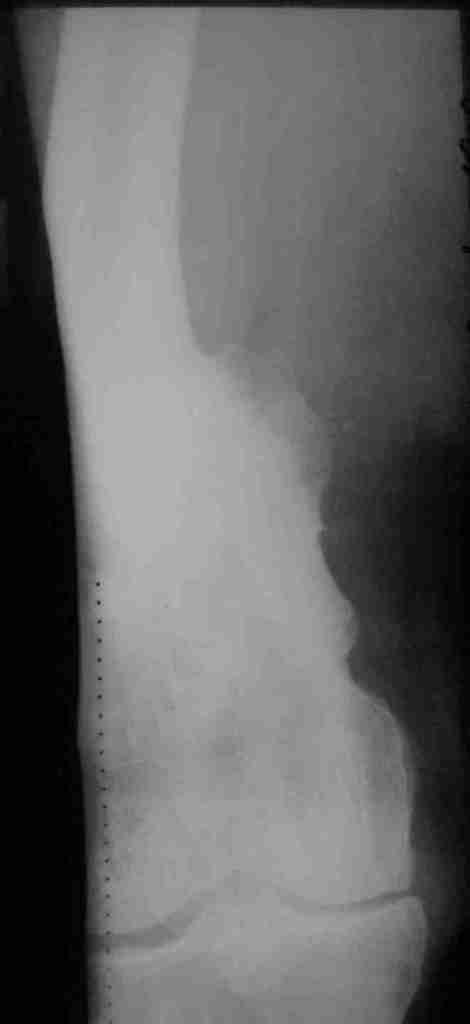

Пациент 69 лет. лечился по поводу перелома н/3 левого бедрамного лет

назад: несостоятельность внутреннего синтеза - АВф- хр. остеомиелит,

свищевая форма с периодическими рецидивами. Результат - укорочение

левого бедра 8 см.

В приложении рентгенограммы и внешний вид бедра.

Имя     : прямая Т.JPG